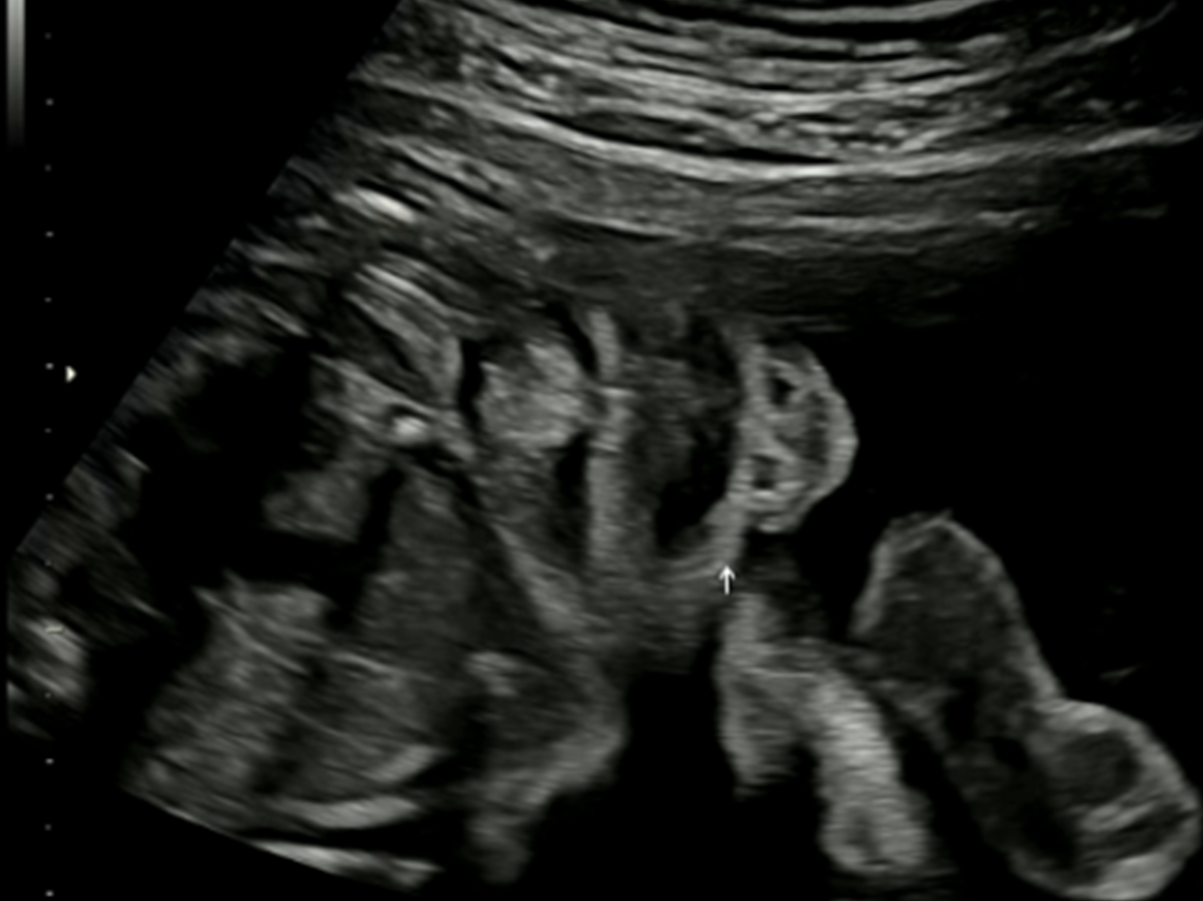

손가락

※ 초음파 용어) LT.HAND : 왼쪽 손가락, RT.HAND : 오른쪽 손가락

손가락도 5개 다 있음을 확인하였다.